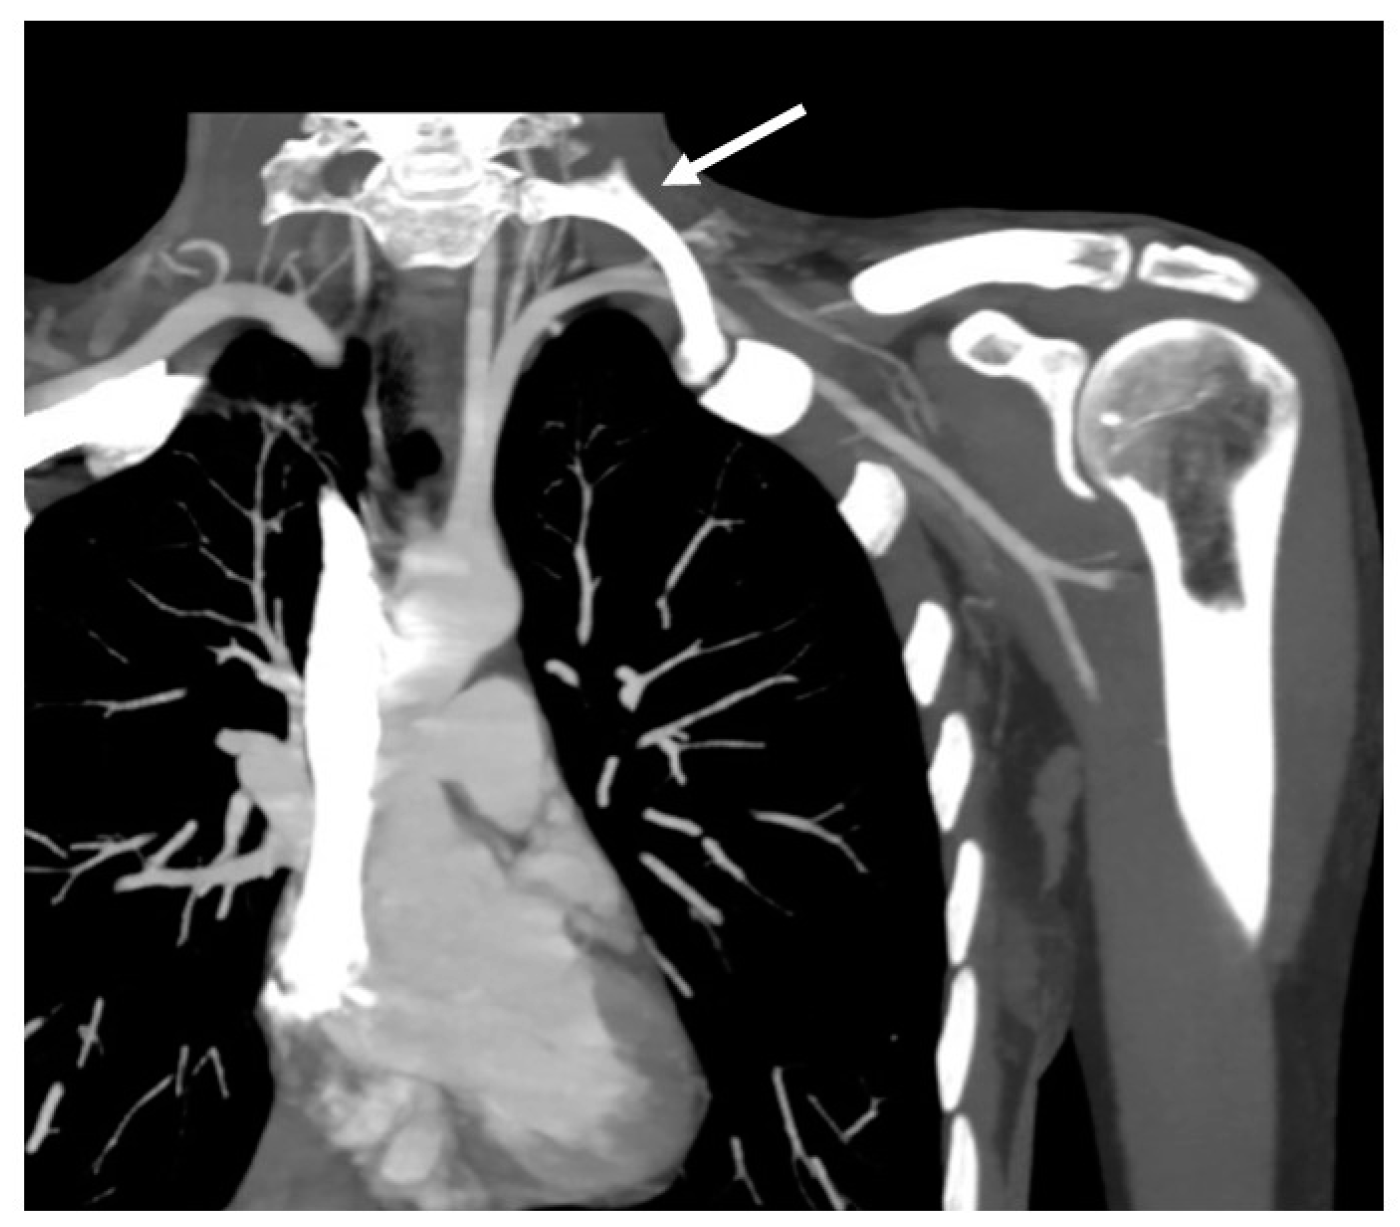

4.3. Computed Tomography (CT)